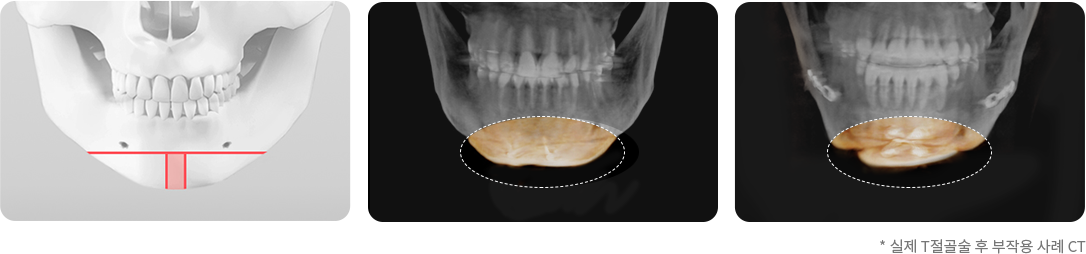

기존의 효과 없는 T절골술

• 턱끝의 모양이 자연스럽지 않으며 튼튼하지 않고 부작용 발생 가능성 높음

기존 T 절골술의 경우 턱끝을 T자 모양으로 절제하고 모아서 고정하는 방법으로 턱끝의 길이와 넓이를 효과적으로 조절할 수 없으며, 턱끝이 넓은 U자 모양이 되거나 울퉁불퉁한 경우가 있습니다. 그리고 절골선이 신경과 치아뿌리에 가까워 수술 후 부작용 발생 가능성이 있습니다.

• 기존의 턱끝 수술 방법인 T 절골술은 턱끝의 길이를 조절할 수 없으며, 수술 후 턱끝이 너무 넓은 U 자형이 됩니다. 그리고 절골선이 신경과 치아뿌리에 가까워 신경이나 치아 손상의 위험이 높습니다.